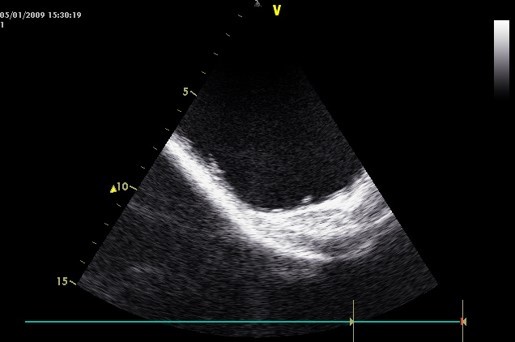

You discover a very enlarged hydronephrotic right kidney her left kidney appears normal

•The kidney has a soft tissue mass;